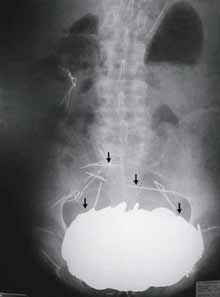

An X-Ray, made of the stomach of a 62-year-old man who came to the emergency room of Cholet General Hospital in western France in 2002. [AP Photo]

Still, doctors were awed when they took an X-ray. They discovered an enormous opaque mass in his stomach that turned out to weigh 12 pounds — as much as some bowling balls. It was so heavy it had forced his stomach down between his hips.